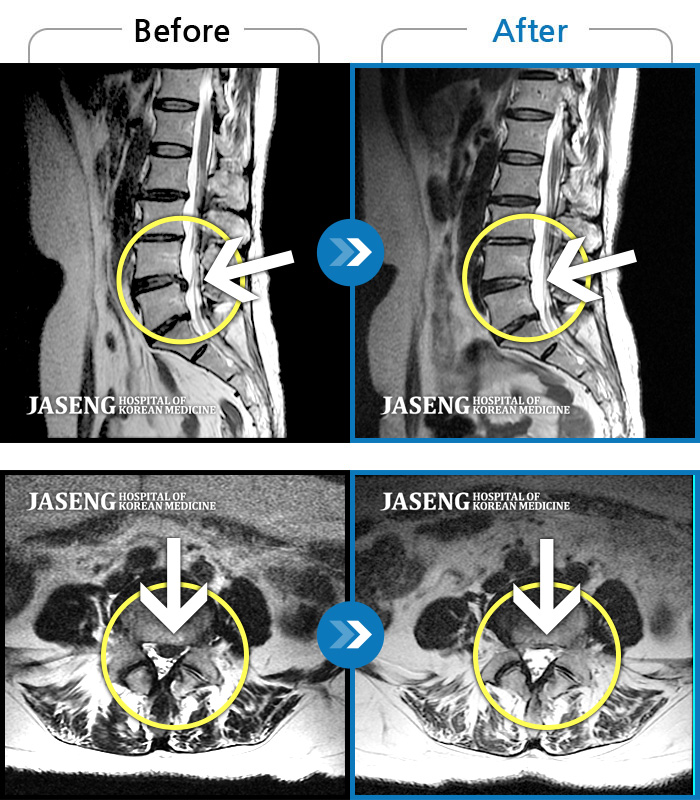

No.58 조회수 163 2023.02.24

No.56 조회수 99 2022.07.15